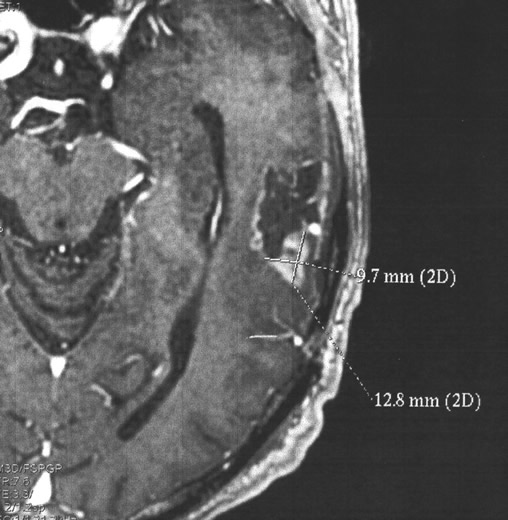

Le 9 décembre, l'IRM laisse apparaître, par rapport à celle du mois d'août, une « composante charnue pariétale périphérique à prédominance postéro-inférieure » avec réapparition d'un œdème. C'est donc négatif, on décèle la réinstallation « classique » de la tumeur.